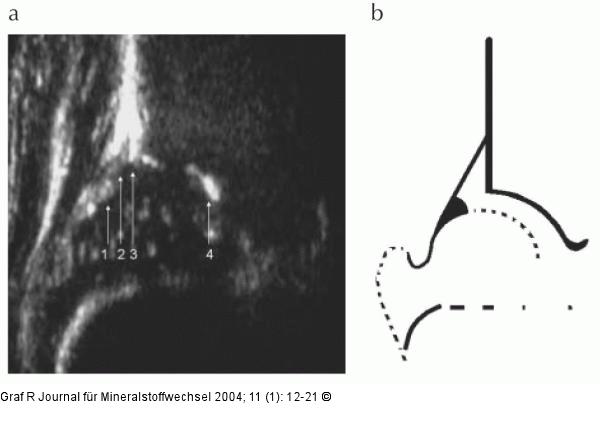

Abbildung 2a-b: Hüftgelenk 2a: Hüftsonogramm eines 2 Wochen alten Säuglings. Der Hüftkopf ist gut von der knöchernen Pfanne abgegrenzt, die vom Unterrand des Os ilium (4) bis zum knöchernen Erker (3) reicht. Das knorpelig hyalin präformierte Pfannendach (2) wird an der Peripherie durch das faserknorpelige Labrum acetabulare (1) begrenzt. 2b: Schema zu Abb. 2a |

Abbildung 2a-b: Hüftgelenk